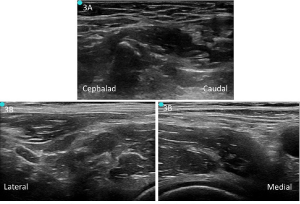

Figure 3. A: Unlabeled preprocedure scan of infrainguinal approach. B: Unlabeled preprocedure scan of suprainguinal approach.